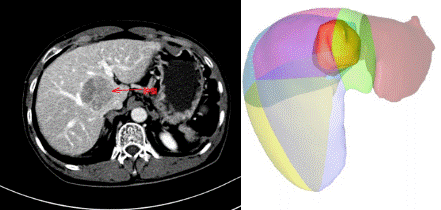

“手术很顺利,术中出血仅500毫升。”患者在重症监护室严密监护一天后转回普通病房,术后没有出现出血和胆漏等并发症,通过10多天的康复顺利出院。胡伟表示,精准和微创是21世纪外科发展的主题。科室始终贯穿这一理念,在追求彻底清除目标病灶的同时,确保剩余肝脏结构完整和功能性体积最大化,最大限度控制手术出血和全身创伤侵袭,最终实现让患者获益最大化。

精准、微创,最大限度的保留了正常肝组织(红色标记为肝脏劈开和肿瘤切除后的痕迹)